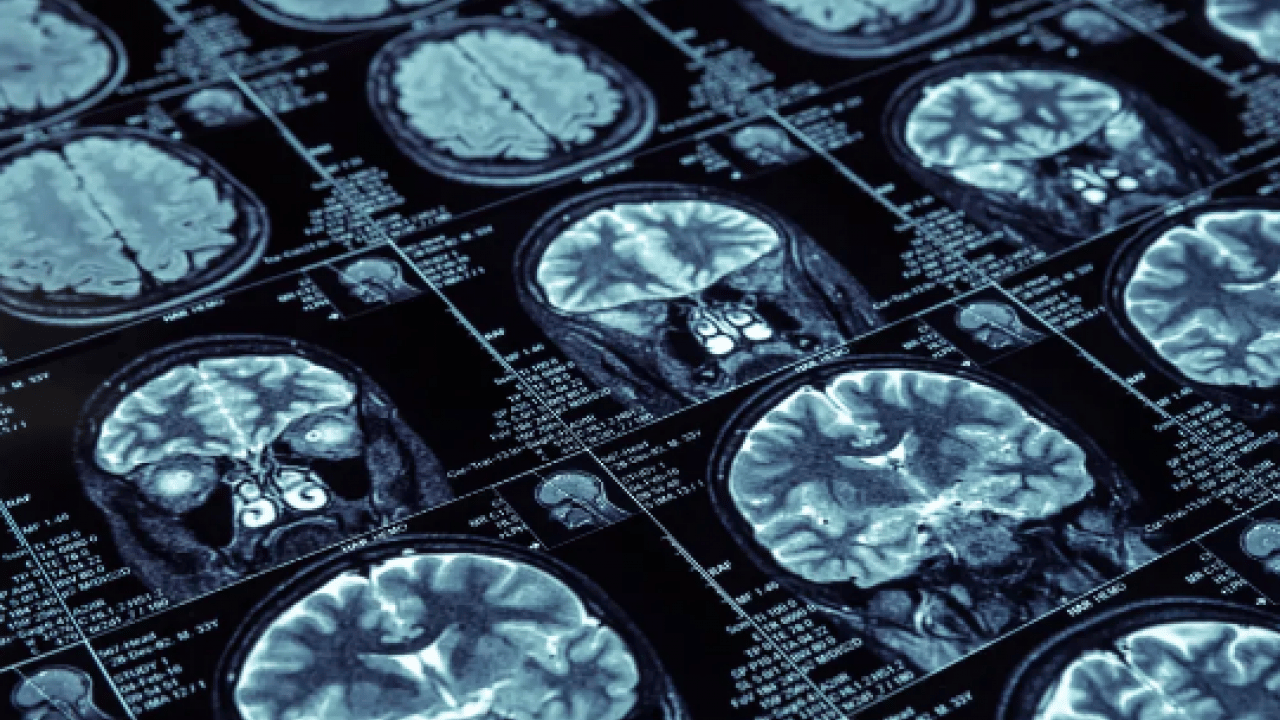

İrlanda’daki Galway Üniversitesi öncülüğünde yürütülen uluslararası çalışmada, D vitamini düzeylerinin beyin sağlığı üzerinde sanılandan daha önemli bir rol oynayabileceği vurgulandı.Araştırma kapsamında, ortalama 39 yaşında ve demans belirtisi bulunmayan 793 yetişkinin kanındaki D vitamini değerleri ölçüldü.

Yaklaşık 16 yıl sonra katılımcıların beyin taramaları yapılarak Alzheimer ile ilişkili tau ve amiloid beta protein düzeyleri incelendi.

Çalışmada, orta yaşta daha yüksek D vitamini seviyelerine sahip bireylerde, ilerleyen yıllarda Alzheimer ile bağlantılı biyobelirteçlerin daha düşük düzeylerde görülebileceği belirlendi.

Araştırmanın yazarlarından Martin David Mulligan, yüksek D vitamini seviyelerinin beyinde tau birikimine karşı koruyucu olabileceğine işaret etti. Öte yandan araştırmacılar, bulguların yalnızca bir bağlantı ortaya koyduğunu, D vitamininin tau seviyelerini doğrudan azalttığını ya da demans riskini düşürdüğünü kanıtlamadığını aktardı.Çalışmanın detaylarına, Neurology Open Access dergisinde yer verildi.